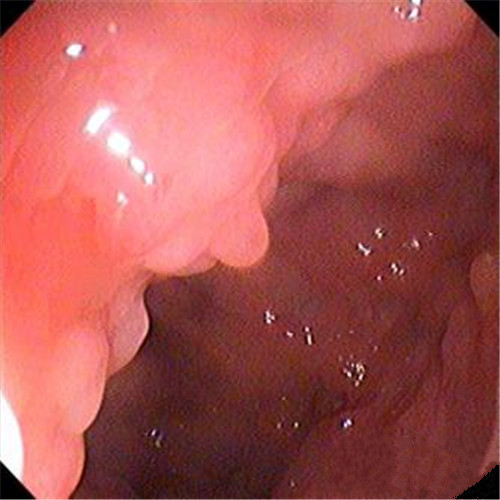

潰瘍性結腸炎乳頭狀